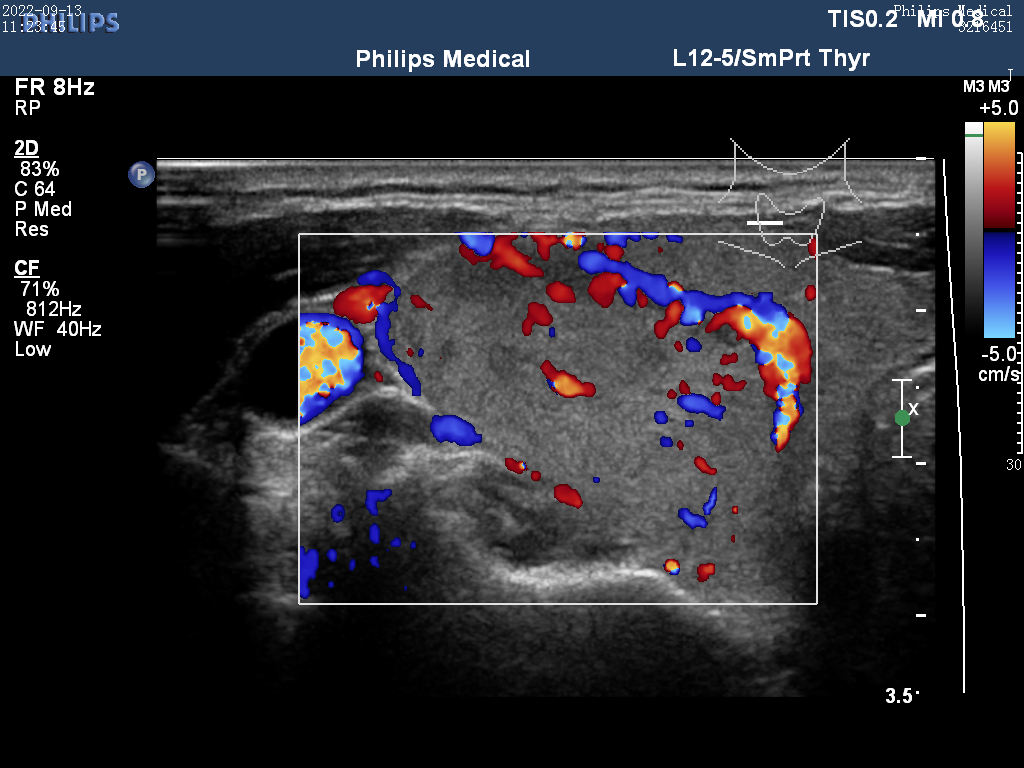

Ultrasound

ID: 171a3d75-2ee5-4b9e-9a21-aa9d23c25798...171a3d75-2ee5-4b9e-9a21-aa9d23c25798

25 yoshli Erkak

16.12.2025 22:04

Yuqori

Tashxis

Malignant (Xavfli)

Saraton xavfi aniqlandi - Zudlik bilan onkolog va endokrinolog bilan bog'laning!

Ishonch

100,0%

TSH

2,5

Tugun

1,5 sm

Yuklab olingan (23x)

Ko'rish